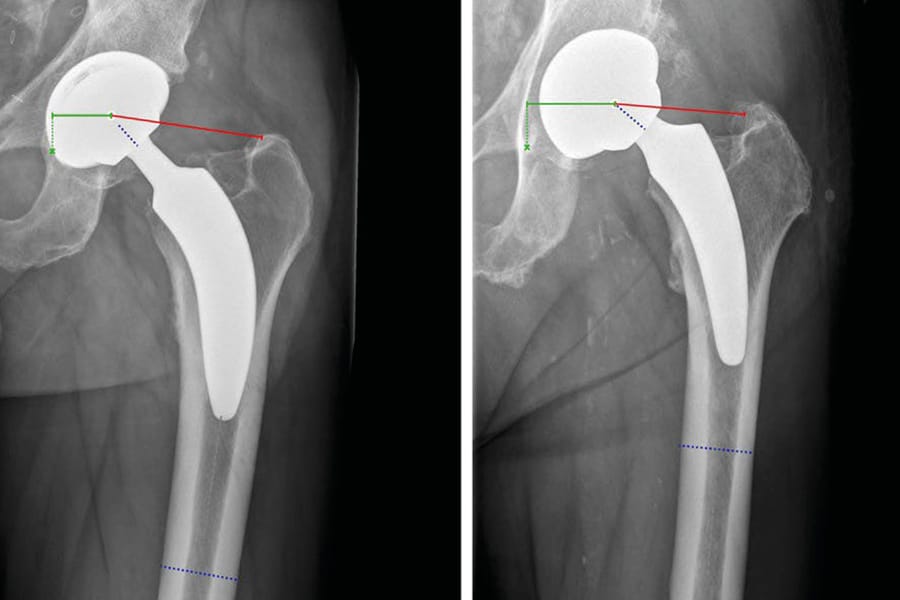

This month, we are honored to feature an interview with Professor Eleftherios Tsiridis, reflecting on a career defined by scientific curiosity and leadership in European orthopedics. The issue broadly examines the evolution of hip arthroplasty, offering critical updates on the biomechanics of Dual Mobility systems and the long-term efficacy of third-generation highly cross-linked polyethylene (XLPE).

Clinical articles in this edition address the pursuit of anatomical restoration, comparing short-stem versus standard prostheses and detailing the piriformis-preserving STAR approach. We also explore the complex management of Developmental Dysplasia of the Hip (DDH) and evaluate advanced solutions for revision surgery, including the BioBall® modular adapter and custom 3D-printed acetabular implants for severe bone defects.